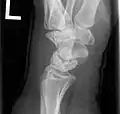

Negative ulnar variance.

Some Kienböck's patients present with an abnormally large difference in length between the radius and the ulna, termed "ulnar variance", which is hypothesized to cause undue pressure on the lunate, contributing to its avascularity. In cases with such a difference, radial shortening is commonly performed. In this procedure, the radius (the lateral long bone) is shortened by a given length, usually between 2 and 5 mm, to relieve the pressure on the dying lunate. A titanium plate is inserted to hold the newly shortened bone together.